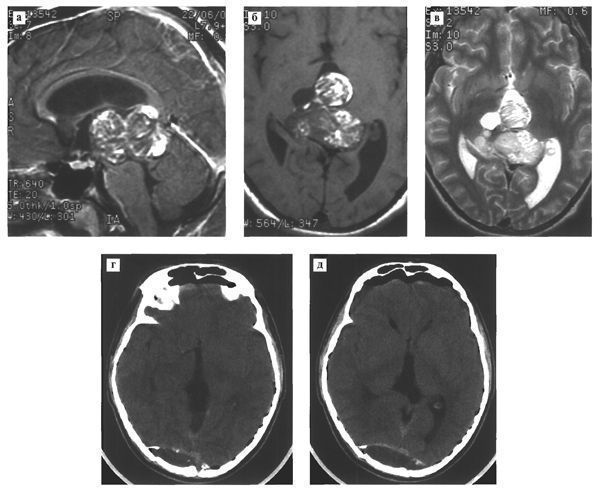

Рис.120. МРТ в режимах Т1 с контрастным усилением (а,б) и Т2 (в) выявляет гетерогенного строения опухоль больших размеров, практически полностью занимающую весь третий желудочек. Средний мозг грубо сдавлен и деформирован. КТ (г,д) после удаления опухоли затылочным транстенториальным доступом не выявляет се остатков. Под костным лоскутом в затылочной области определяется эпидуральная гематома.

Клинический пример

Рис. 121. Злокачественная тератома третьего желудочка и пинеальной области ребенка 10 лет с синдромом преждевременного полового развития.КТ (а) выявляет большую гетерогенного строения опухоль третьего желудочка с множественными кистами и петрификатами. В переднем роге бокового желудочка расположена дренажная трубка.

При МРТ в режимах T1 (б) и T2 (в,г) определяется большая опухоль, полностью заполняющая просвет третьего желудочка и вызывающая окклюзионную гидроцефалию. В толще опухоли содержатся множественные кисты, жир. Контрольная КТ (е,ж,з) после удаления опухоли с применением переднего транскаллезного субхороидального доступа. Опухоль удалена практически полностью

Обращает внимание выраженный коллапс мозга и образование субдуральных гигром.